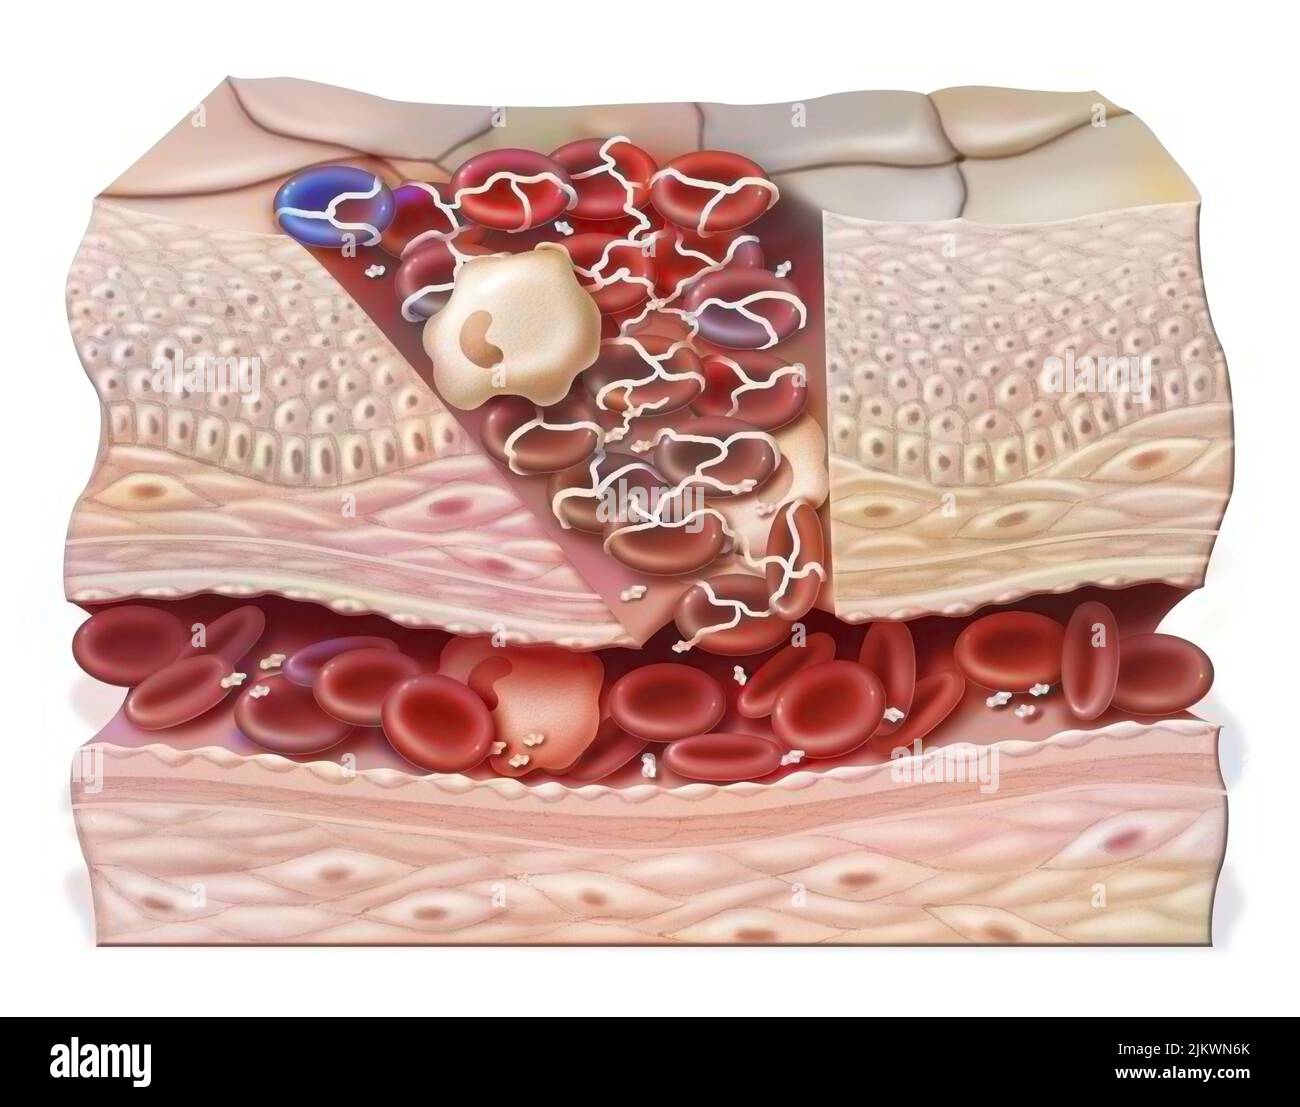

RF2JKWR54–Vaisseau sanguin contenant des globules rouges, des globules blancs, des plaquettes et du plasma.